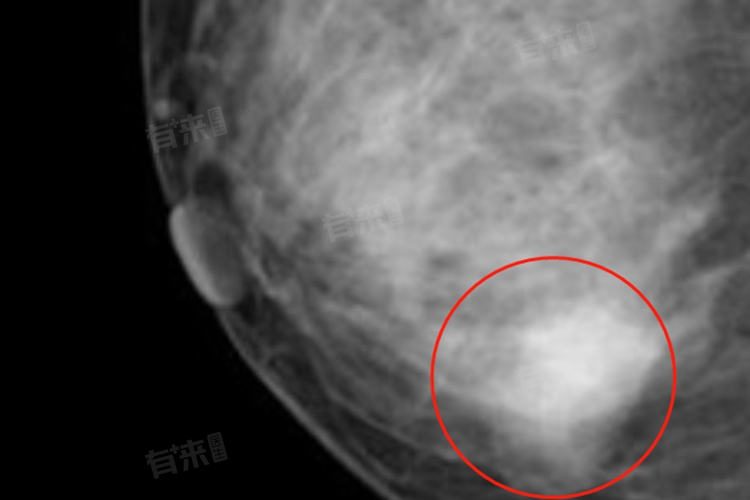

- 在影像学检查中,结节影通常表现为与周围正常组织密度不同的区域,可能是高密度或低密度影。在影像学上,结节通常具有明确的边界和形状,可以是实性、囊性或囊实性的。其大小也常被用来描述结节的特征,如肺结节通常以直径小于3厘米为界定。